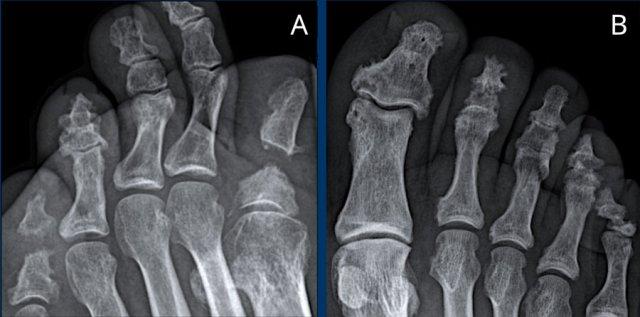

A

Tổn thương ăn mòn tại các khớp PIP 2-5 và DIP 3-5.

Biến dạng cánh hải âu điển hình tại DIP 3 (mũi tên trắng).

Dính khớp PIP 4 (mũi tên vàng), xuất hiện ở giai đoạn muộn của bệnh.

B

Hẹp khe khớp kèm ăn mòn trung tâm. Biến dạng cánh hải âu tại PIP 2-4, DIP 2 và khớp CMC-1.

Dính khớp DIP 3. Lệch trục về phía trong của PIP 2.

Tư thế chụp “ball catcher” (tư thế chụp nghiêng chéo) của hai bàn tay ở bệnh nhân viêm xương khớp ăn mòn.

Có tổn thương lan rộng hai bên tại các khớp liên đốt (IP).

Lưu ý phân bố đối xứng và không ảnh hưởng đến các khớp bàn ngón tay (MCP).

Hình ảnh biến dạng cánh hải âu điển hình tại các khớp DIP, còn được gọi là ăn mòn dạng hải âu hoặc hình răng cưa.

Đây là hình ảnh kinh điển trong viêm xương khớp ăn mòn, nhưng cũng đã được ghi nhận trong viêm khớp vảy nến và viêm khớp dạng thấp.